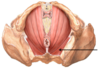

Pelvic diaphragm

Layer of muscles under pelvic organs

Keeps guts from falling out of butts

Co-opted tail muscles

Contracts during orgasm